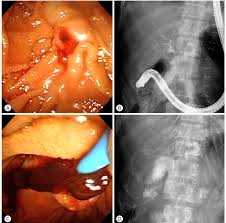

La hemobilia ocurre por la existencia de una fístula entre la vía biliar y el territorio de la porta o la arteria hepática. El cuadro clínico, la tríada de Quincke se caracteriza por ictericia (60%) ¬según el grado de obstrucción del conducto biliar por los coágulos¬, dolor en hipocondrio derecho (70%) y sangrado digestivo, cuyo espectro abarca desde una anemia secundaria a un sangrado crónico inadvertido hasta un sangrado gastrointestinal (alto [60%] o bajo [90%]) submasivo con hipotensión, shock e incluso fallecimiento (lo cual no es común), como en el caso que nos ocupa, donde los aspectos novedosos no sólo residen en el origen tumoral, sino en la forma de presentación clínica, que no corresponde a esta etiología, que suele ser lenta y recidivante, y no súbita y masiva como ocurrió.

Para el diagnóstico se dispone de múltiples exámenes complementarios tales como: imágenes (ecografía abdominal, tomografía computada, angio TC, resonancia magnética), endoscopía y la angiografía, no sólo como herramienta diag¬nóstica sino también como modalidad terapéutica de elección. La ecografía abdominal es una técnica útil para establecer el diagnóstico, al detectar la presencia de coágulos en la vesícula o vía biliar, o demostrando lesiones estructurales que justifiquen el sangrado. Otras exploraciones complementarias que pueden utilizarse son la tomografía computarizada abdominal, la colangiorresonancia, la gammagrafía con eritrocitos marcados con tecnecio, la colangiopancreatografía retrógrada endoscópica y la colangiografía transhepática percutánea. También se puede realizar mediante la arteriografía del tronco celíaco, localizando el punto de sangrado si hay un débito adecuado.